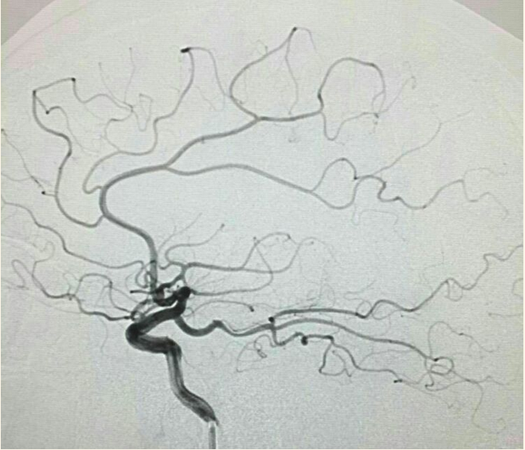

支架打开后:

最后造影:

术后第二天查看患者无不适,言语流利,四肢肌力5级,精神状态好转。继续双抗治疗。